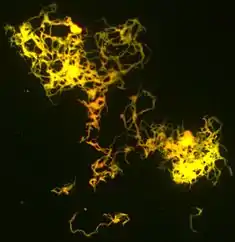

Cord factor, or trehalose dimycolate (TDM), is a glycolipid molecule found in the cell wall of Mycobacterium tuberculosis and similar species. It is the primary lipid found on the exterior of M. tuberculosis cells.[1] Cord factor influences the arrangement of M. tuberculosis cells into long and slender formations, giving its name.[2] Cord factor is virulent towards mammalian cells and critical for survival of M. tuberculosis in hosts, but not outside of hosts.[3][4] Cord factor has been observed to influence immune responses, induce the formation of granulomas, and inhibit tumor growth.[5] The antimycobacterial drug SQ109 is thought to inhibit TDM production levels and in this way disrupts its cell wall assembly.[6]

A cord factor molecule is composed of a sugar molecule, trehalose (a disaccharide), composed of two glucose molecules linked together. Trehalose is esterified to two mycolic acid residues.[7][8] One of the two mycolic acid residues is attached to the sixth carbon of one glucose, while the other mycolic acid residue is attached to the sixth carbon of the other glucose.[7] Therefore, cord factor is also named trehalose-6,6'-dimycolate.[7] The carbon chain of the mycolic acid residues vary in length depending on the species of bacteria it is found in, but the general range is 20 to 80 carbon atoms.[3] Cord factor's amphiphilic nature leads to varying structures when many cord factor molecules are in close proximity.[3] On a hydrophobic surface, they spontaneously form a crystalline monolayer.[9] This crystalline monolayer is extremely durable and firm; it is stronger than any other amphiphile found in biology.[10] This monolayer also forms in oil-water, plastic-water, and air-water surfaces.[1] In an aqueous environment free of hydrophobic surfaces, cord factor forms a micelle.[11] Furthermore, cord factor interlocks with lipoarabinomannan (LAM), which is found on the surface of M. tuberculosis cells as well, to form an asymmetrical bilayer.[1][12] These properties cause bacteria that produce cord factor to grow into long, intertwining filaments, giving them a rope- or cord-like appearance when stained and viewed through a microscope (hence the name).[13]